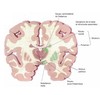

vue d’ensemble cordon postérieur - Lemniscus médial

A

image

How well did you know this?

1

Not at all

2

De quoi est composé les NGC ?

composé de noyaux sous corticaux - Noyau caudé. - Le Putamen. - Le Globus pallidus - Le Noyau sous-thalamique. - La substance noire. * L’ensemble formé par le Noyau caudé et le Putamen est dénommé Striatum. = Noyau caudé + Putamen = Striatum.

38

que constitue le striatum ?

Il constitue la cible majeure des afférences corticales aux NGC.

39

que représente le globus pallidus &

Il représente l’origine de la projection vers le thalamus.

40

les autres structures des NGC participent à quoi ?

Ils participent à des boucles internes diverses qui modulent l’activité du circuit principal.

41

Quel est le rôle principal des NGC ?

Les noyaux gris centraux sont les principaux constituants du système moteur extra-pyramidal.

42

Les NGC interviennent dans quoi ? (4 principaux)

- L’initiation du mouvement. - Suppression des mouvements indésirables. - S’assure du maintien du mouvement jusqu’à la fin. - Régulation du tonus musculaire.

43

Pathologies associées aux NGC ? quoi ? quels sont les symptômes de cette maladie ?

* La maladie de Parkinson (1% de la population au-dessus de 50 ans). * Symptômes de la maladie de Parkinson: ----» Hypokinésie, réduction considérable de la capacité de réalisation des mouvements: - Bradykinésie (mouvements volontaires lents). - Akinésie (difficultés à initier certains mouvements musculaires). - Rigidité. - Tremblements.

Représentation schématique des boucles liant le cortex cérébral aux NGC avant le retour cortical vers l’aire 6